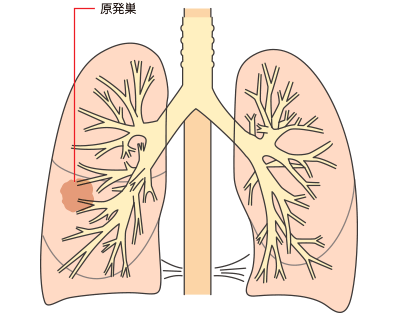

その他、肺がんはがんの発生部位によって肺門型肺がんと肺野型肺がんに分けられます。

| 肺門型肺がん |

| 肺野型肺がん |

肺門型肺がんと肺野型肺がん